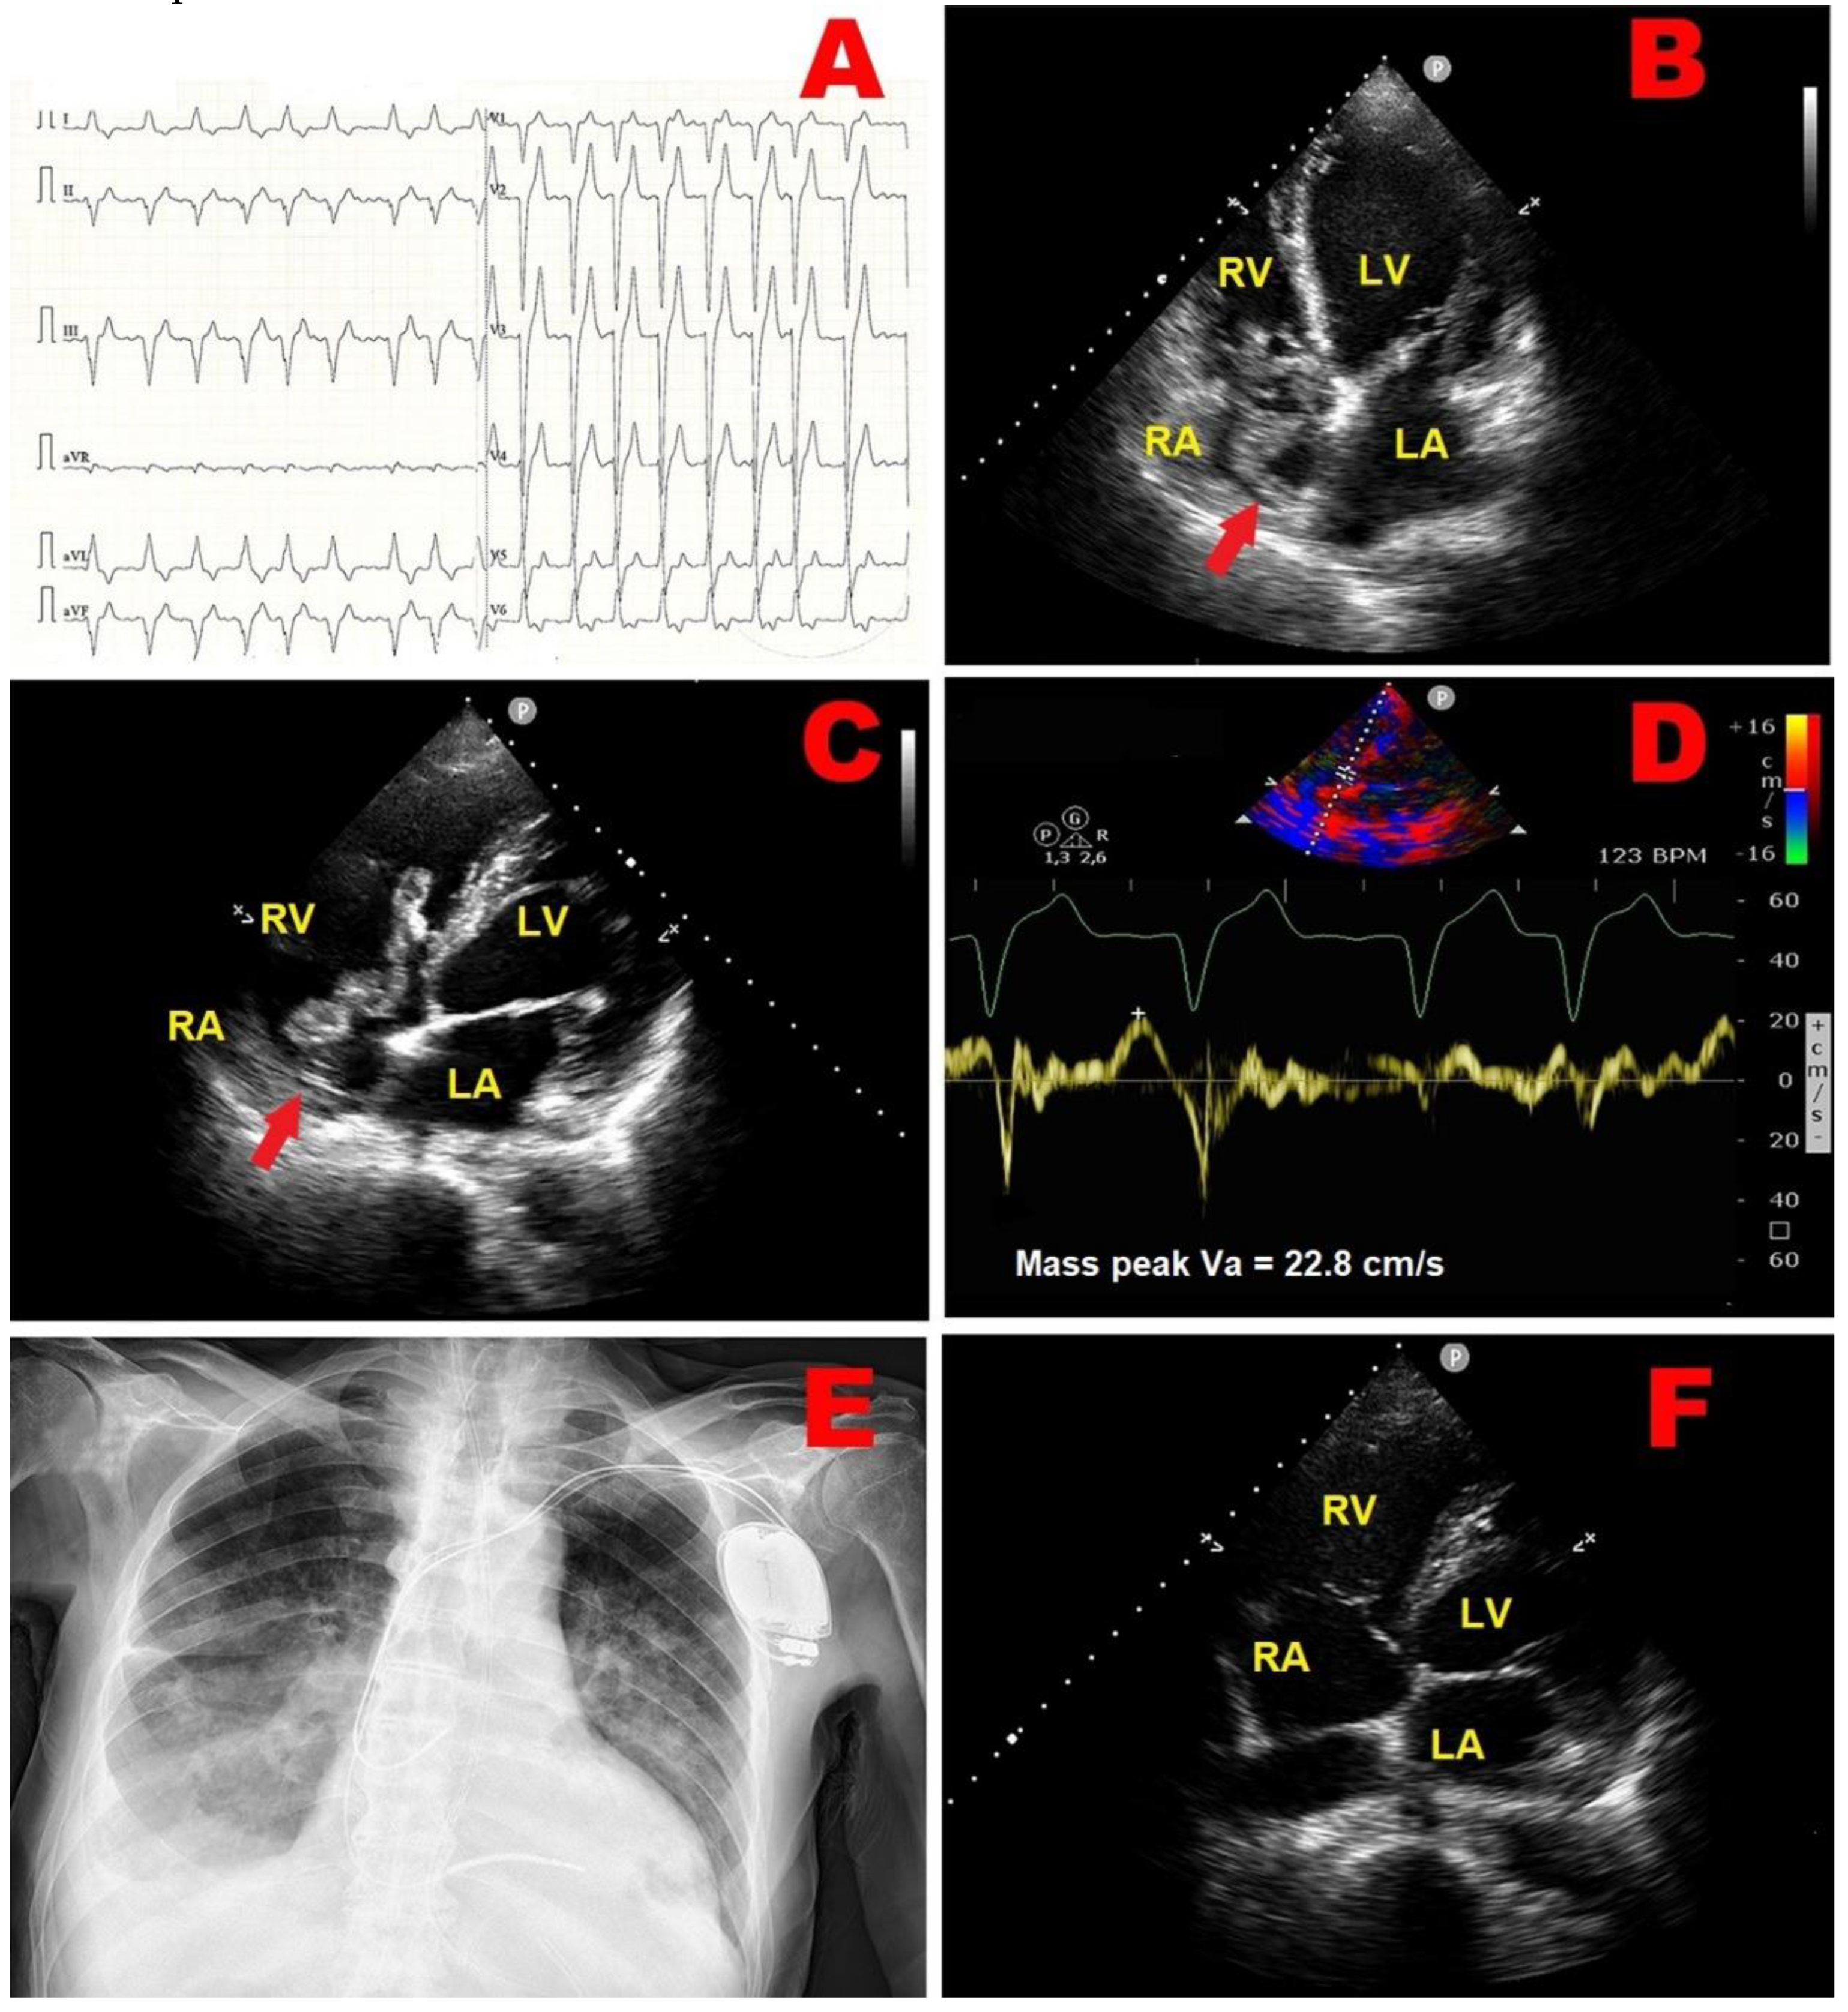

2.1. Clinical Case 1

2.2. Clinical Case 2